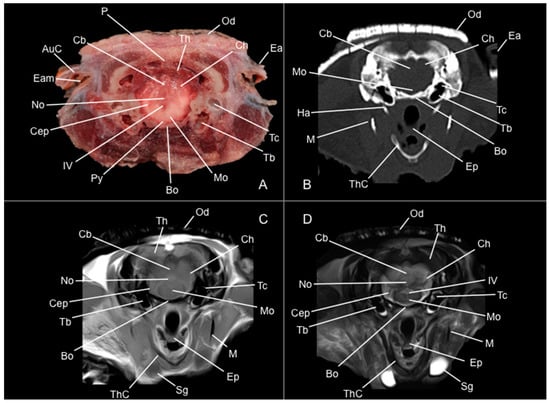

3. Results

3.1. Anatomical Study

3.2. Computed Tomography Study

3.3. Magnetic Resonance Imaging (MRI)